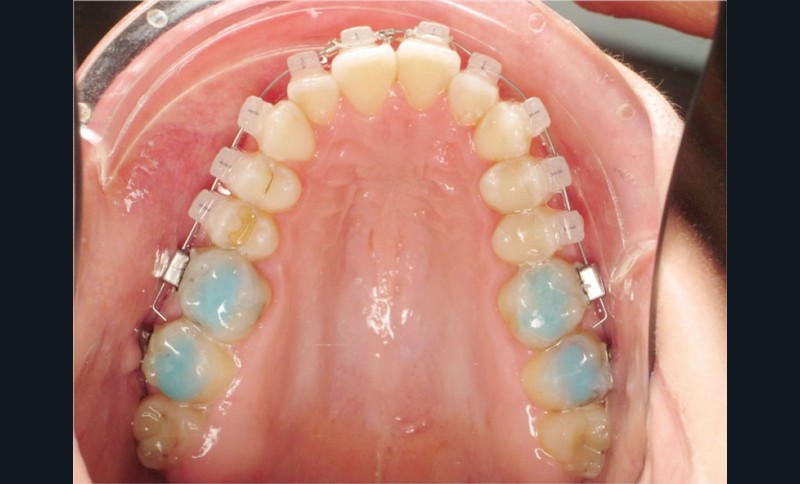

La patiente demande des attaches céramiques et nous trouvons un compromis en lui proposant un appareillage Insignia Damon Clear au maxillaire et Damon métallique à la mandibule.

L’avantage des brackets métalliques en technique Insignia est l’individualisation complète des informations des 1er, 2e et 3e ordres (torque individuel suivant set up).

Des surélévations postérieures par cales sont posées et nous avons prévu un port d’élastiques précoce 23 heures sur 24.